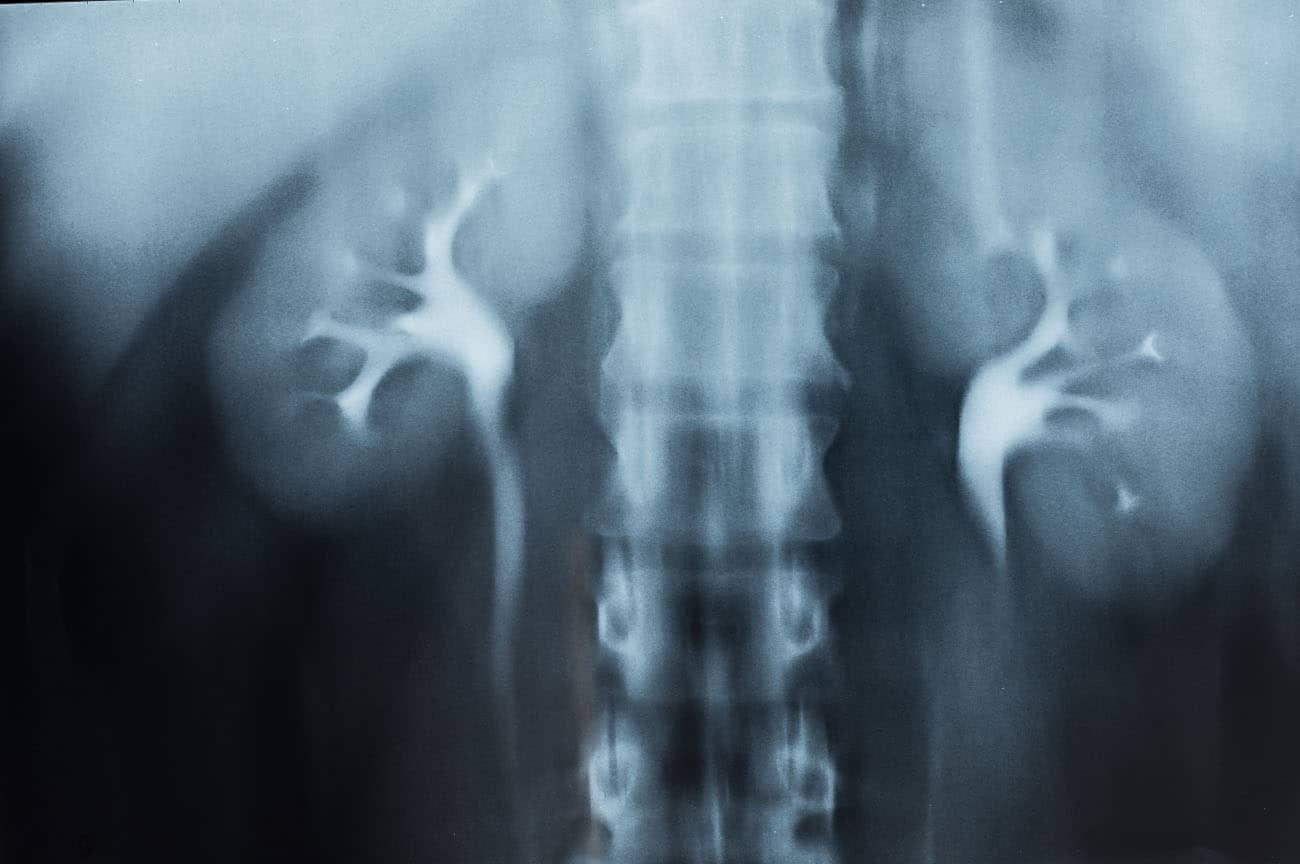

Incidências OPD e OPE da urografia excretora

Urografia excretora oblíquas com 30°.

Justificativa para realização do exame

Visualizar sinais de infecção, traumatismo e obstrução dos rins ou obstrução do ureter distal (bilateral).

Principais estruturas demonstradas

O rim do lado mais elevado é mais bem demonstrado nas oblíquas, já o ureter do lado mais baixo é projetado longe da coluna, evitando-se sobreposições indesejáveis das duas estruturas. A critério clínico devem-se realizar as duas oblíquas, como método comparativo eficiente.

Fatores técnicos e posicionamento

• DFF: 1m.

• Tamanho do filme/receptor de imagem e sentido: 35x43cm no sentido longitudinal.

• Técnica de referência: 2mAs e 75KV, na mesa.

• RC: perpendicular no centro do filme e ao nível das cristas ilíacas.

• Posição do paciente e da parte ou região do corpo: paciente em decúbito dorsal inicialmente e girar o corpo em um ângulo de 30° para direita ou para esquerda.

• Respiração: parar a respiração e expor durante e expiração.